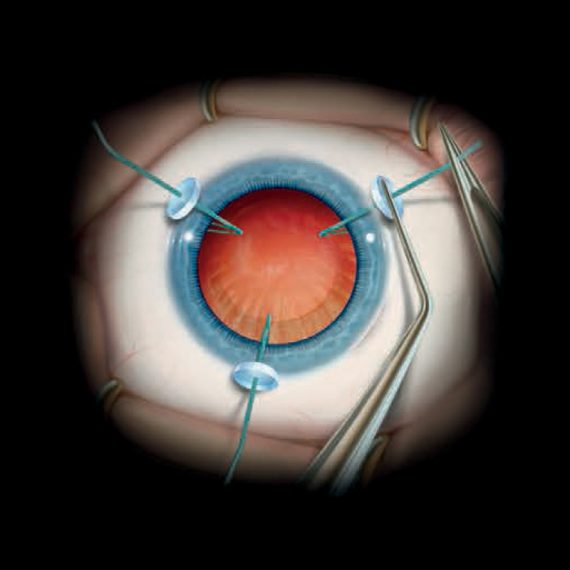

MST capsule retractorsMST Capsule Retractors provide stable support for the capsular...Code: MCR-0001, MCR-0002Explore

MST capsule retractorsMST Capsule Retractors provide stable support for the capsular...Code: MCR-0001, MCR-0002Explore -

MST Malyugin Ring®Exclusive to IQ Medical, the MST Malyugin Ring® provides...Code: MAL-0001, MAL-0002, MAL-1001, MAL-1002Explore

MST Malyugin Ring®Exclusive to IQ Medical, the MST Malyugin Ring® provides...Code: MAL-0001, MAL-0002, MAL-1001, MAL-1002Explore -

Phakos iris retractorsPhakos iris retractors provide a simple, reliable solution for...Code: MVRI22Explore

Phakos iris retractorsPhakos iris retractors provide a simple, reliable solution for...Code: MVRI22Explore -